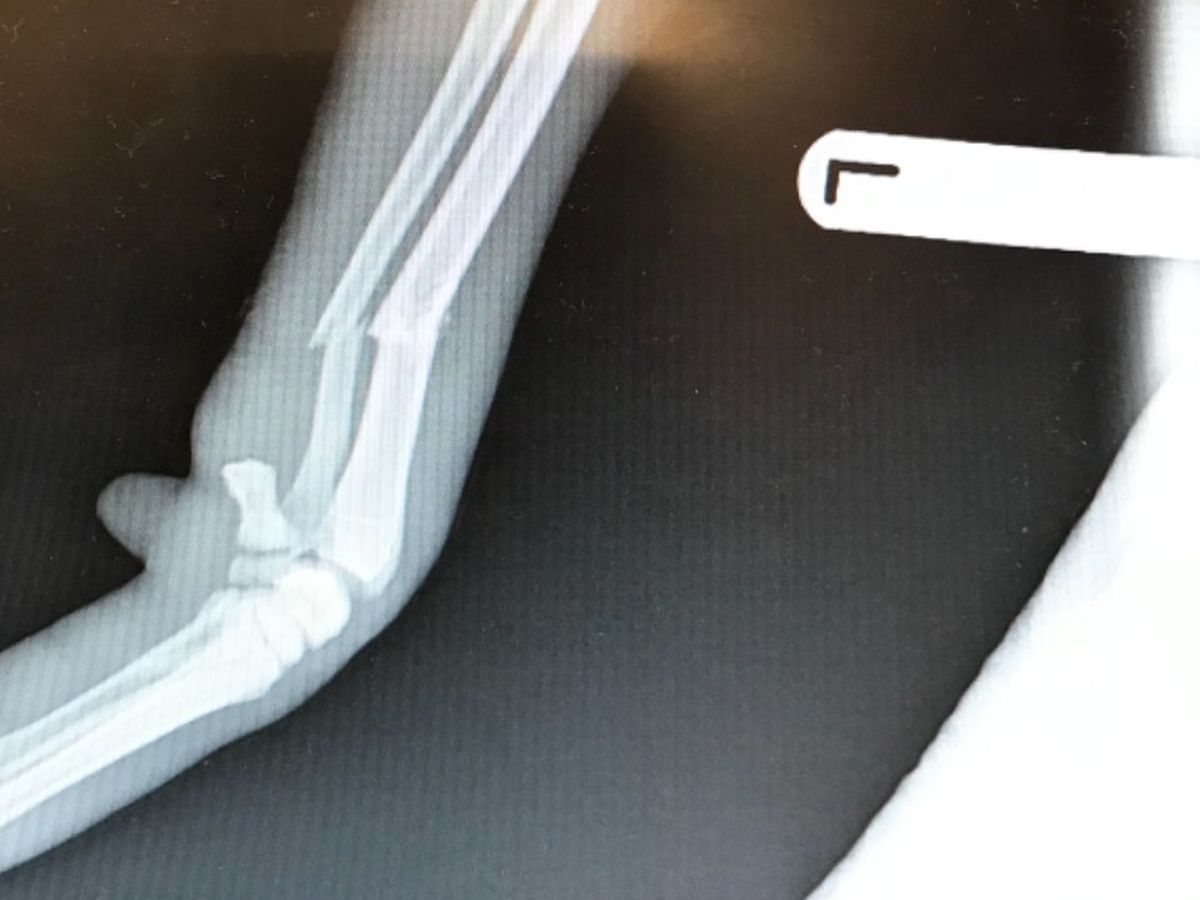

We received a call today from our vets regarding a stray lurcher with a broken front leg due to be put to sleep tonight and I’m desperately trying to save him.

he has an open fracture and his nose is cut and grazed and other grazes to his legs and feet. He’s in a bad way but he was so waggy and pleased to see me.